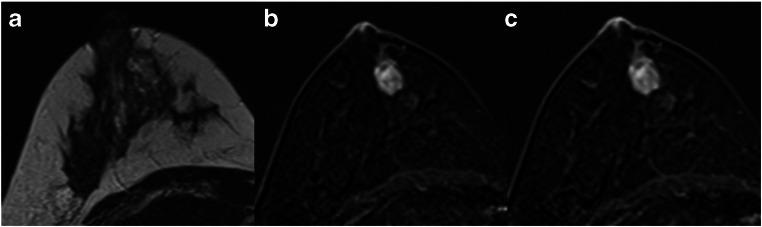

This retrospective study included 183 consecutive, histologically proven, suspicious (MR BI-RADS 4) lesions detected within our local high-risk screening program. All lesions were evaluated according to the Kaiser score for breast MRI by three readers blinded to the final histopathological diagnosis. The Kaiser score ranges from 1 (lowest, cancer very unlikely) to 11 (highest, cancer very likely) and reflects increasing probabilities of malignancy, with scores greater than 4 requiring biopsy. Receiver operating characteristic (ROC) curve analysis was used to evaluate diagnostic accuracy.

There were 142 benign and 41 malignant lesions, diagnosed in 159 patients (mean age, 43.6 years). Median Kaiser scores ranged between 2 and 5 in benign and 7 and 8 in malignant lesions. For all lesions, the Kaiser score's accuracy, represented by the area under the curve (AUC), ranged between 86.5 and 90.2. The sensitivity of the Kaiser score was high, between 95.1 and 97.6% for all lesions, and was best in mass lesions. Application of the Kaiser score threshold for malignancy (≤ 4) could have potentially avoided 64 (45.1%) to 103 (72.5%) unnecessary biopsies in 142 benign lesions previously classified as BI-RADS 4.